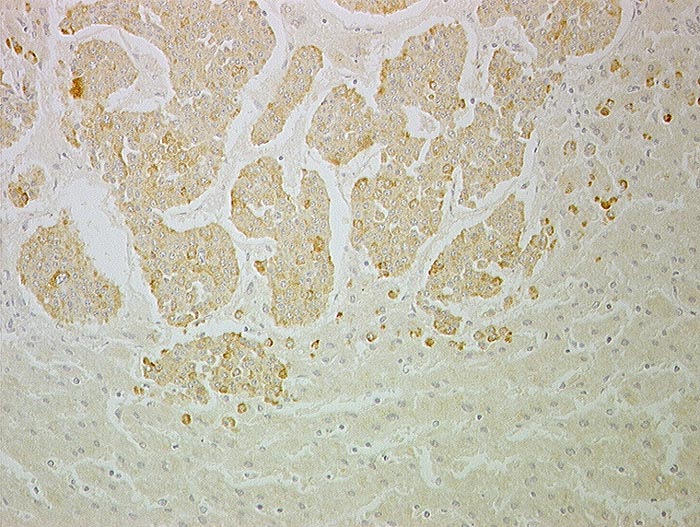

PathoPic ID 1245 - Neuroendokriner Tumor des Ileums : Metastase

Neuroendokriner Tumor des Ileums : Metastase

Leber

Monomorphe Tumorzellen in soliden insulär angeordneten Nestern. Zwischen den Nestern feine Blutgefässe.

Immunhistochemie

Synaptophysin